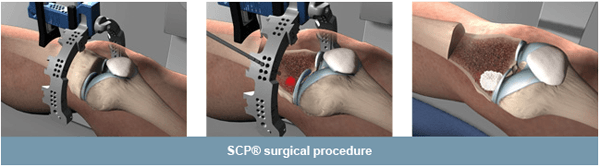

The Subchondroplasty™ procedure is a minimally invasive surgery designed to treat subchondral defects associated with chronic bone marrow edema (BME) by filling them with a hard-setting, biomimetic bone void filler.

The SCP® procedure is performed either alone or in conjunction with other arthroscopic treatments (meniscus treatment, cartilage treatment)

The SCP® procedure is designed to access and treat subchondral defects associated with chronic BME. The SCP® procedure does not treat or repair damage to the cartilage, ligaments, meniscus, or synovial tissue.

During the procedure, your surgeon will use a guide instrument to access the subchondral defect and fill it with a bone substitute to allow new, healthy bone to repair the defect.